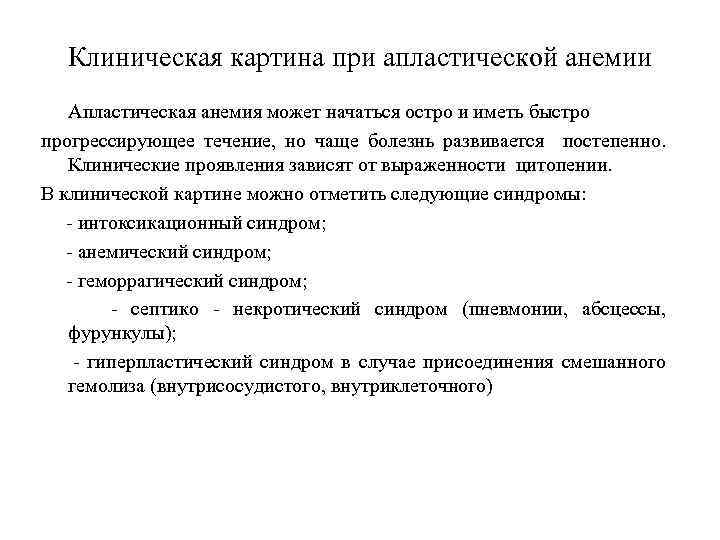

Клиническая картина при апластической анемии Апластическая анемия может начаться остро и иметь быстро прогрессирующее течение, но чаще болезнь развивается постепенно. Клинические проявления зависят от выраженности цитопении. В клинической картине можно отметить следующие синдромы: - интоксикационный синдром; - анемический синдром; - геморрагический синдром; - септико - некротический синдром (пневмонии, абсцессы, фурункулы); - гиперпластический синдром в случае присоединения смешанного гемолиза (внутрисосудистого, внутриклеточного)